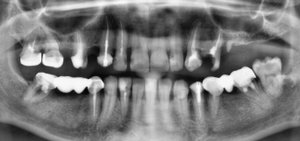

Отвалилась старая пломба, которую ставили девять лет назад. Пришел к стоматологу, она осмотрев сказала, что надо зачистить и заново запломбировать. Начав процедуру чистки, она попробовала пошатать зуб, потом сказала, что нужно сделать снимок. Снимок сделали, ее вердикт — надо удалять зуб, поскольку пошло воспаление вокруг корней, если его лечить со штифтами или еще как, через некоторое время он снова даст о себе знать и все равно придется удалить.

Смысл конечно всегда есть, но если диагноз доктора подтвердится (воспаление на корнях), то скорее всего зуб придётся удалить.